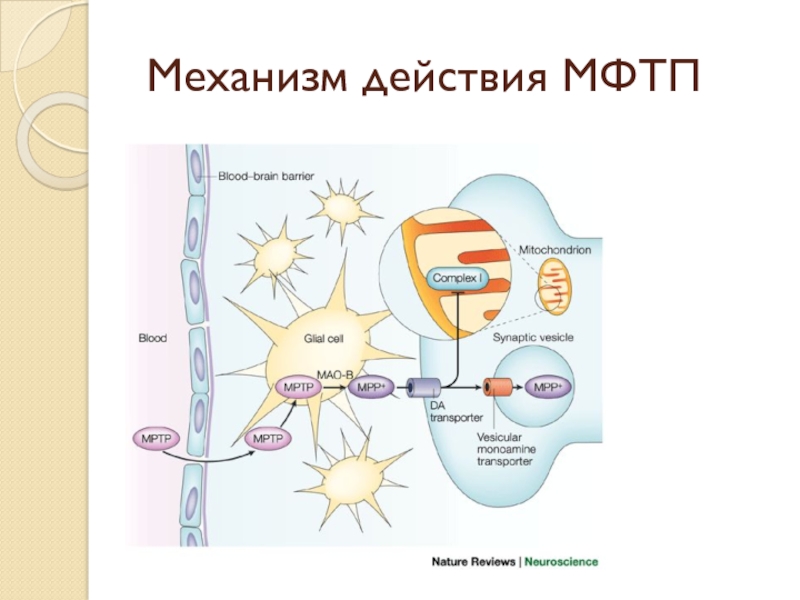

Слайд 3МФТП

Приводит к возникновению симптомов БП и гибели дофаминергических нейронов черной субстанции

у людей, некоторых видов обезьян, мышей.

Благодоря липофильности проникает через ГЭБ.

Под действием МАО-Б окисляется до МФП+ (1-метил-4-фенилпиридина), который проникает в митохондрии и ингибирует комплекс I дыхательной цепи.

Благодоря липофильности проникает через ГЭБ.

Под действием МАО-Б окисляется до МФП+ (1-метил-4-фенилпиридина), который проникает в митохондрии и ингибирует комплекс I дыхательной цепи.